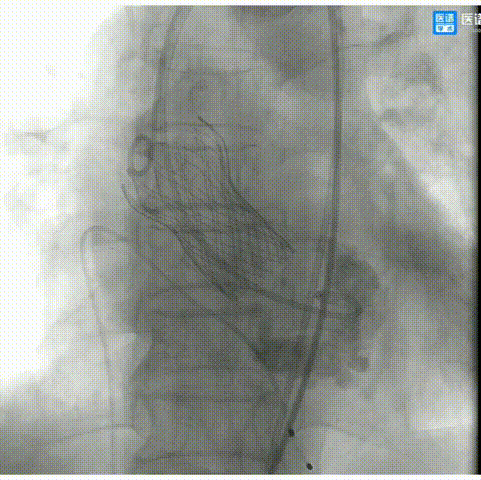

6.造影评估示瓣膜植入深度、工作形态良好、微量瓣周漏,遂予以全部释放;

7.超声显示最大流速降至1.13m/s,平均跨瓣压差约3mmHg;